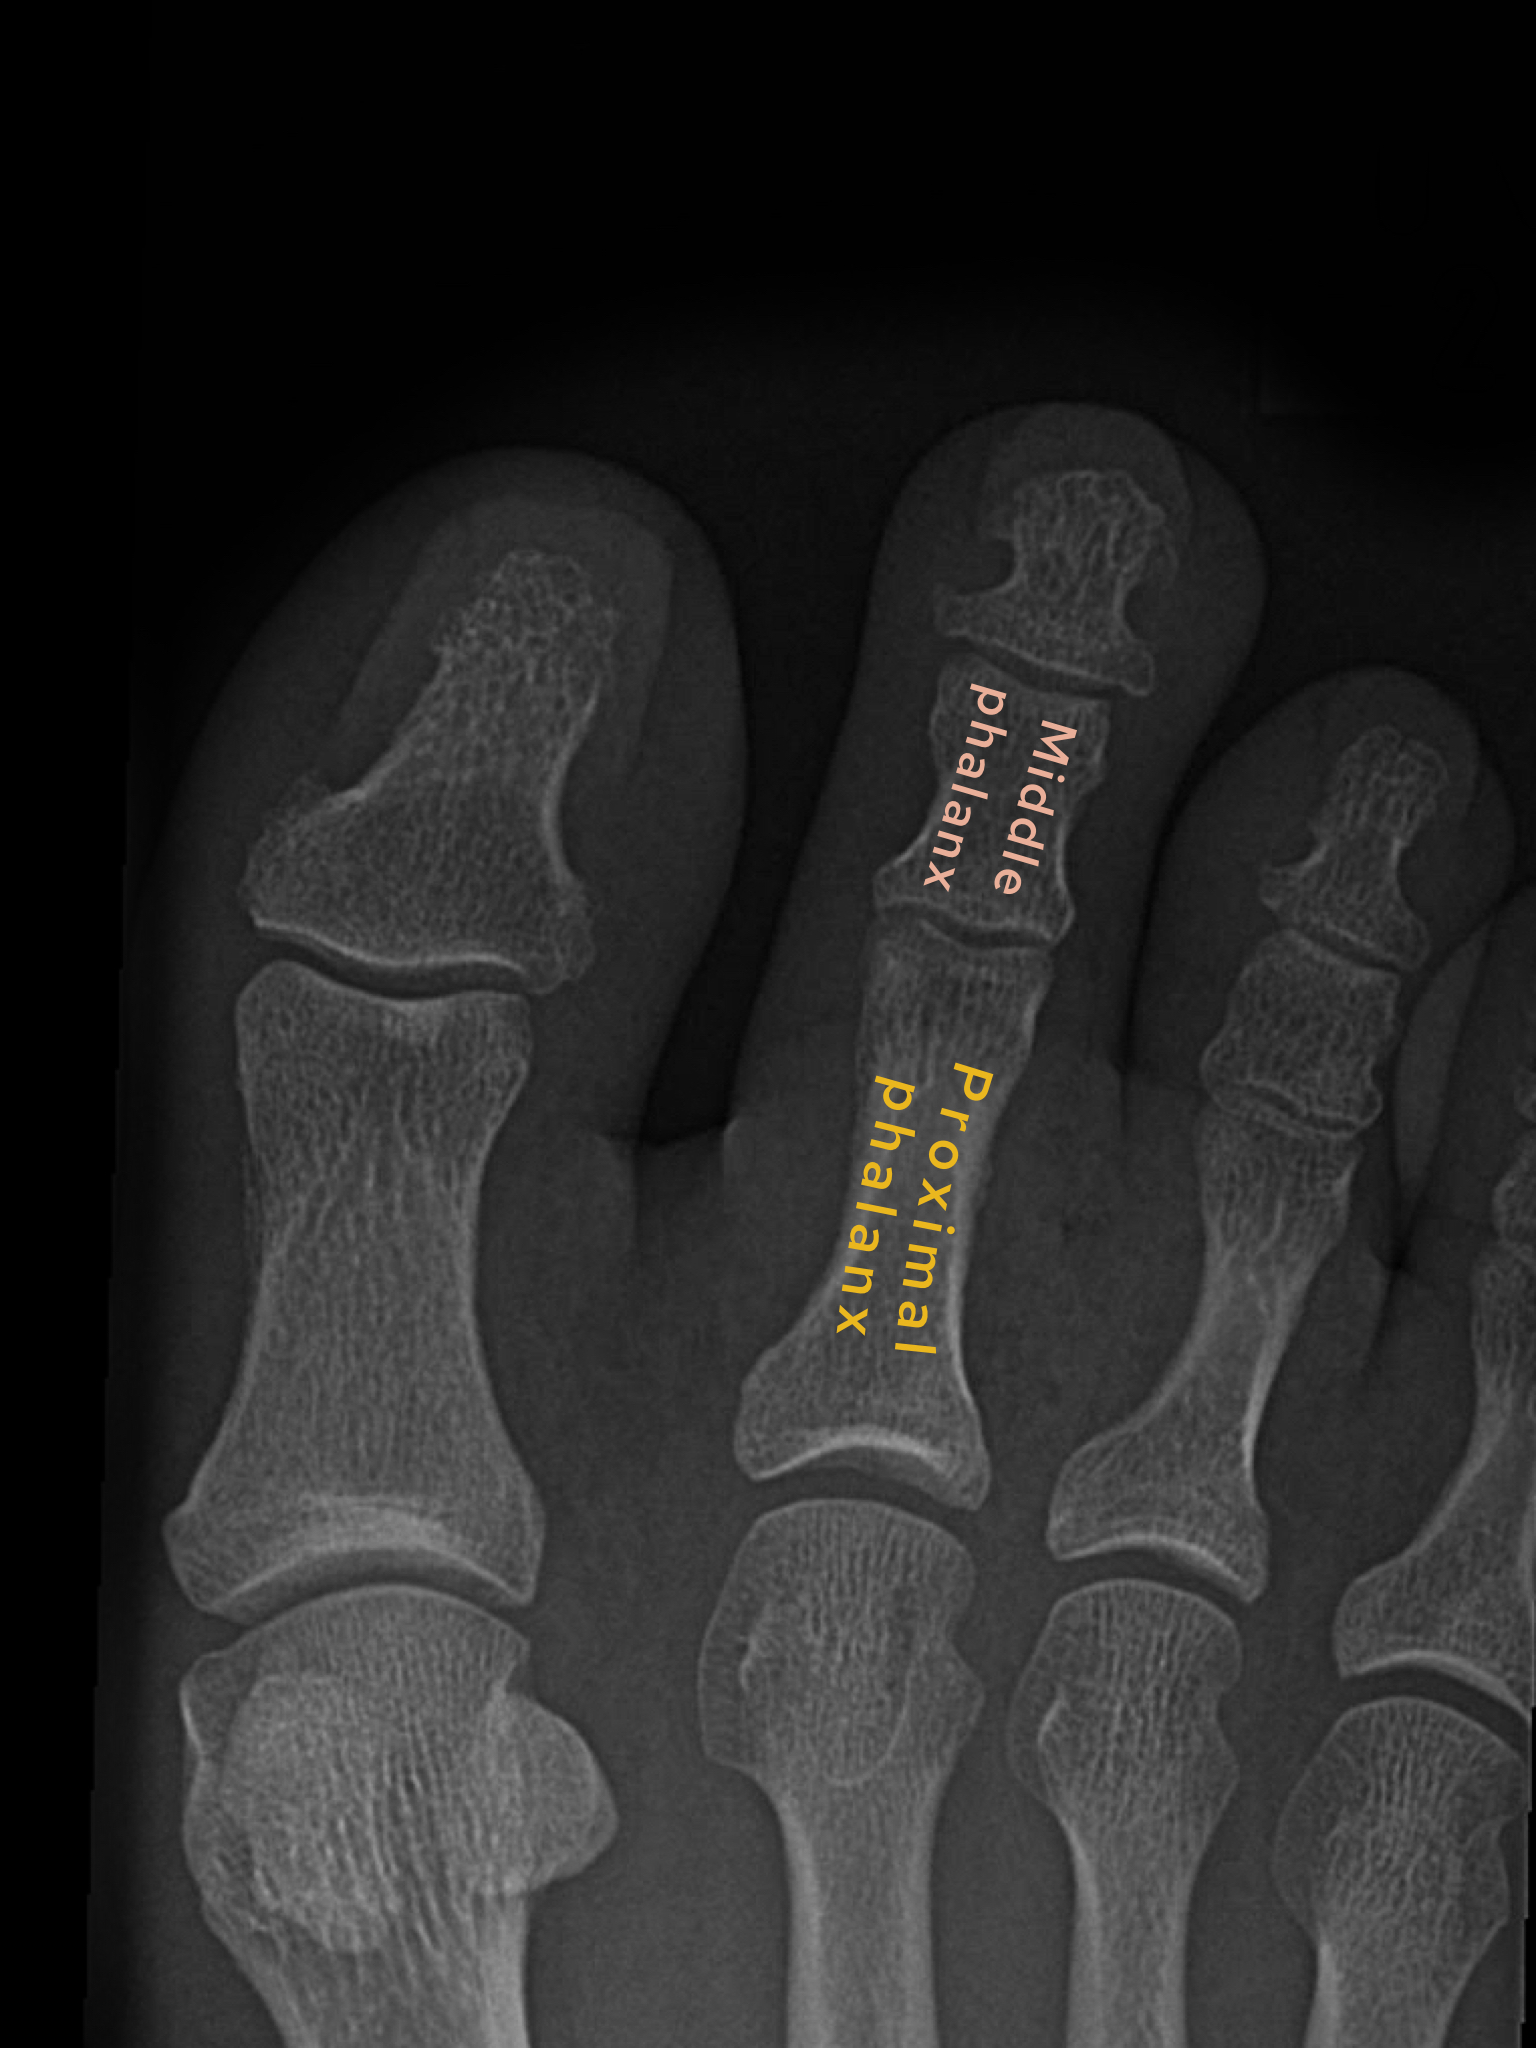

Case 3

A female in her 70s presents with foot pain after trauma. Have a look at her foot X-Ray below:

Choose from one of the following options: